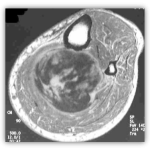

Η απεικόνιση των βλαβών πρέπει να κατευθύνεται από τον Ορθοπαιδικό Χειρουργό και ακολουθεί μία συγκεκριμένη μεθοδολογία.